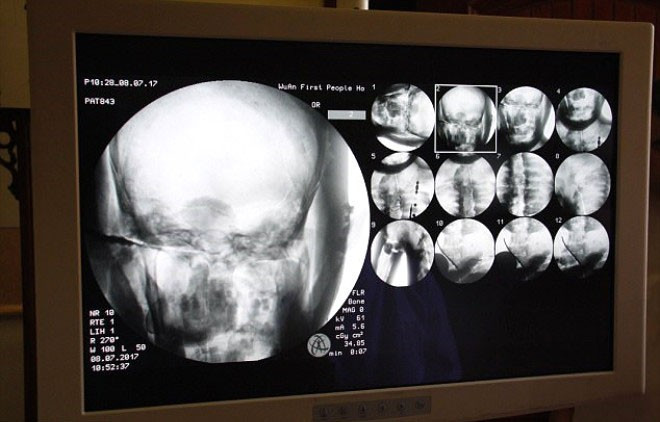

Tapınağın yönetimi, Ci Xian'ın cesedi için CT taramasını 8 Temmuz'da düzenledi. Doktorlar, Usta Ci Xian'ın, hala sağlıklı kemikleri ve bir beyni bulunduğunu söylediğinde, keşişler şok geçirdi.

Yapılan incelemede rahibin kemiklerinin hiç bozulmadığı ve beyninin zarar görmediği ortaya çıktı.

Üst çene, üst dişler, kaburga, omurga hepsi yerinde duruyor.